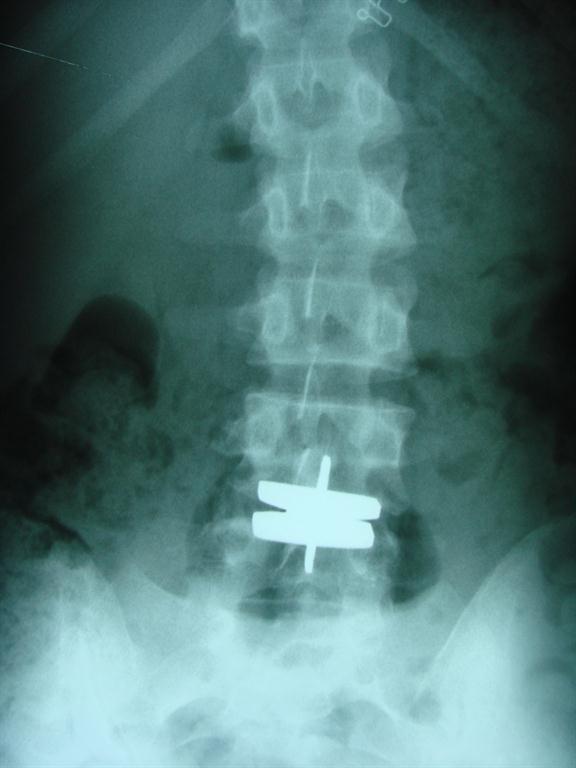

So what is this “adjacent segment disease” that these artificial disc reports mention? It’s a term referring to potential complication of spinal fusion or disc replacement: disc degeneration at the disc level above or below a replaced disc or spinal fusion. For example, if your spine is fused from L3 to L5, the L2 disc may be placed under so much stress that it degenerates. (2) As a matter of fact, 29% of patients who have 3 thoracolumbar levels or more fused experience adjacent level disease. (3) Aurora Chiropractic Center offers chiropractic care with conservative, non-operative care with Cox Technic as the first step in managing spine pain. This care addresses the affected, pain-originating spinal segment in hopes of sparing the adjacent segments.